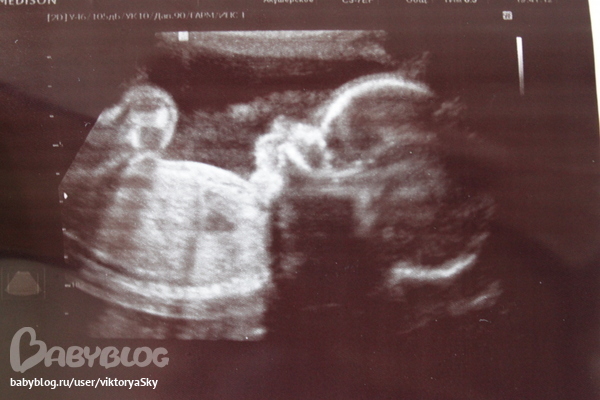

Узи 22 недельки

Узи...С малышом все впорядке,лежит головой вниз,крупный малыш 569 гр. По узи растем активно скелет ребеночка на 23,4 недельки.Лежит зевает,пополам сложился- большие пальчики на ногах у лба))))